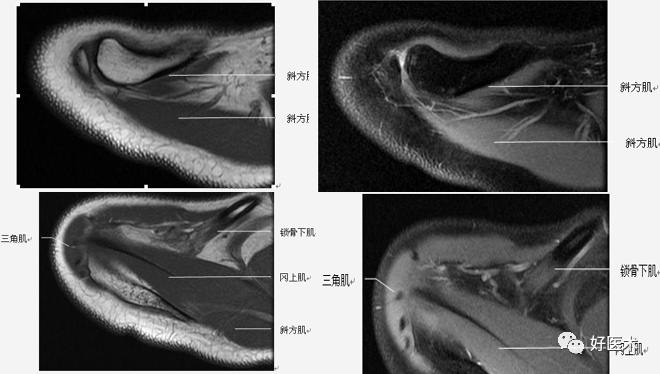

(2)肩袖

肩袖是由冈上肌、冈下肌、小圆肌和肩胛下肌的肌腱构成。前三个肌腱由上向下均止于肱骨大结节,而肩胛下肌腱止于肱骨小结节。

(2)扫描方位

斜冠状位:取横断位作定位像,扫描层面与冈上肌腱平行,扫描范围为锁骨外端至肩峰。

斜矢状位:取横断位作定位像,扫描层面与关节盂平行,扫描范围包括肱骨头和整个关节盂。

斜冠状、斜矢状:显示肩袖及冈上肌走行、显示喙肩弓。